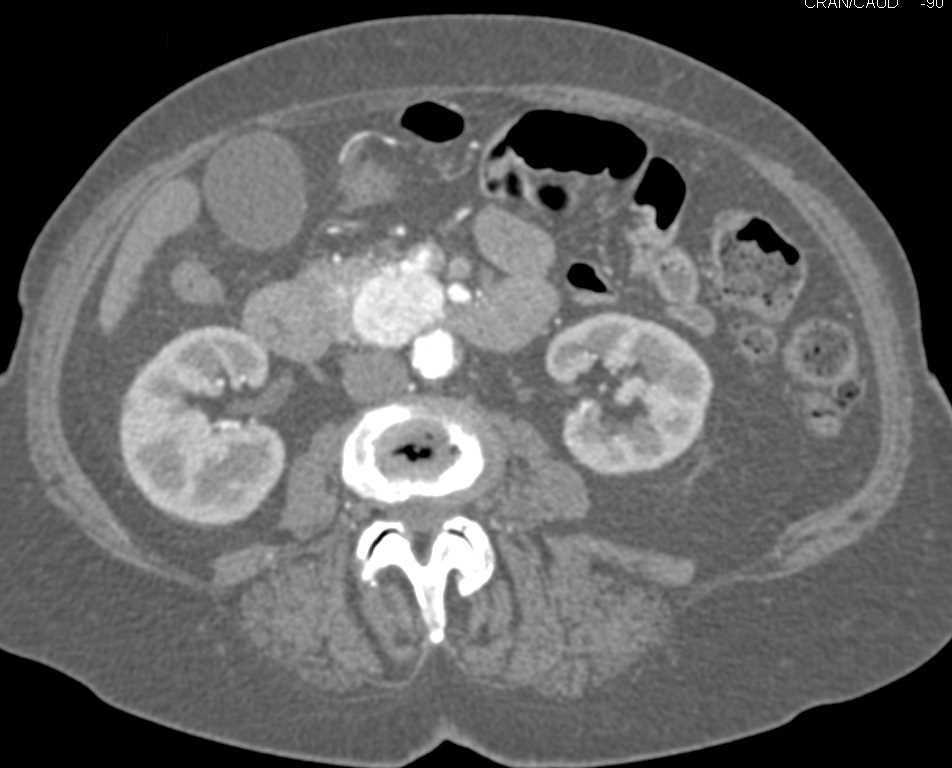

Top Normal Pancreatic Duct